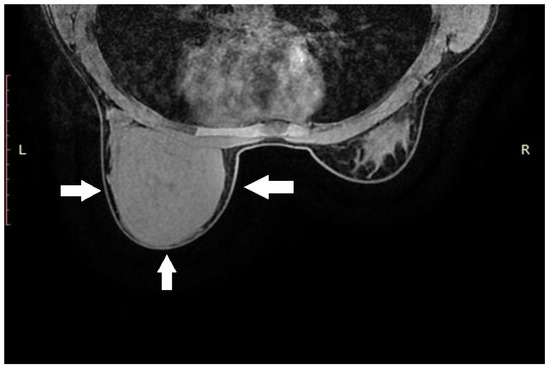

Due to the size of the lesion, diagnostic evaluation was extended to include magnetic resonance imaging (MRI). MRI confirmed the previous findings, showing a well-circumscribed lesion without diffusion restriction. No additional focal pathological changes were detected. No pathological lymph nodes were visualized in either axilla (levels I, II, or III). MRI was classified as BI-RADS category 4 for the left breast and category 1 for the right breast (Figure 1).

Figure 1. Magnetic resonance imaging of the left breast. Axial T1-weighted contrast-enhanced sequence reveals a large, homogeneous tumorous lesion, indicated by white arrows.